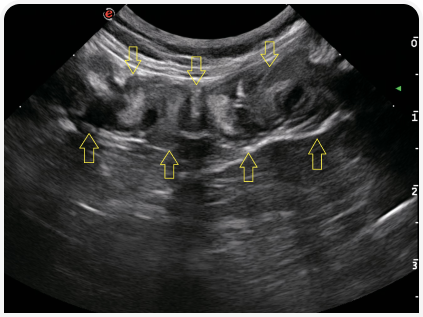

Полезным дополнительным инструментом при поиске причин рвоты может стать ультразвуковое исследование органов брюшной полости. При признаках расслоения стенки кишечника исключают линейные инородные тела (Рисунок 4), хотя иногда такие изменения неверно истолковывают как складчатость (Рисунок 5) — неспецифичный симптом, описанный у кошек при энтерите, панкреатите, перитоните, новообразованиях (5). Также можно оценить изменения архитектоники, например утрату структуры слоев или утолщение стенки ЖКТ.